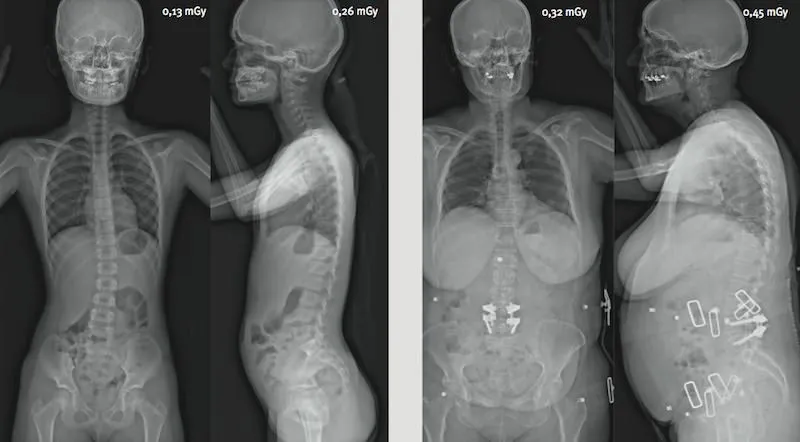

Réduction de dose particulièrement importante pour les jeunes patients

La réduction d’irradiation est encore plus spectaculaire dans le cas des examens répétés comme les suivis de scoliose. De plus, ces suivis concernent bien souvent des patients très jeunes pour lesquels la réduction d’irradiation est encore plus bénéfique. L’analyse statique par EOS est fortement recommandée pour l’imagerie pédiatrique squelettique.

Dose d’irradiation comparée pour un examen corps entier face/profil

Dose comparée EOS / Scanner